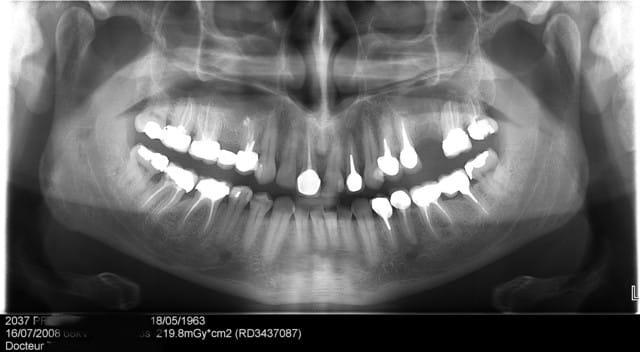

26/04/2009 à 17h06

La première fois ne fût pas agréable, parce qu'il s'agit de mon premier implant perdu!

Le deuxième dépucelage concerne mon premier SINUS LIFT.

salut dentiste 57, je suis comme toi partisan de la pose d'un implant dans ce cas là, la 15 ne me semble plus assez solide pour supporter un bridge. J'ai juste une question : sur la pano il semble y avoir une hauteur osseuse favorable, n'aurait il pas été possible de mettre un implant court ( 8,5 ou 9 mm) avec un petit punch?